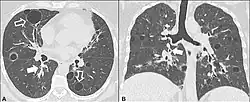

CT scan of lymphocytic interstitial pneumonia, with pulmonary cysts.